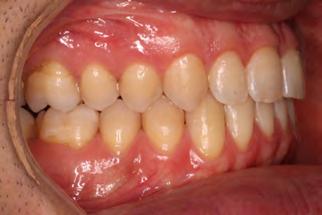

Palatal mini-implants were placed by a periodontist, followed by placement of the rapid palatal expander (RPE) and bonding of the mandibular arch with self-ligating Damon clear braces. Patient had SARPE surgery performed by the oral surgeon three weeks later (Figure 2), and the expander was turned once a day for three weeks (Figure 3). The maxillary arch was then bonded. Both archwires were incremen-

tally upgraded to an 18 x 25 NiTi wire, and the patient was placed on vertical elastics on the right side. With enough space for the tongue, the lateral open bite began to close.

Approximately six months after insertion of the RPE, digital scans were taken for SureSmile custom wires and the patient was scheduled for the SFOT procedure with the oral surgeon. The RPE was removed, SureSmile wires inserted and segmental corticotomies performed, immediately followed by further vertical elastics on the right side (Figure